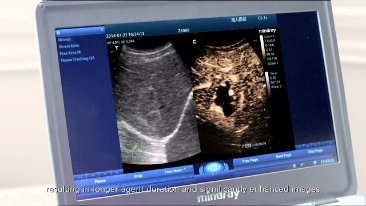

Basado en la plataforma de ultrasonido de nueva generaciĂłn de Mindray, mQuadro, el M9 ha elevado los estĂĄndares industriales a todo un nuevo nivel. Los procesadores de transmisiĂłn y recepciĂłn de se?al avanzados proporcionan una ecodetecciĂłn altamente sensible y precisa. Las tecnologĂas de transductor innovadoras permiten una mejor penetraciĂłn y una resoluciĂłn mĂĄs alta, lo que mejora enormemente su experiencia de diagnĂłstico.

Proporcionando imĂĄgenes mĂĄs nĂtidas, todas las sondas compatibles con el M9 vienen equipadas con la tecnologĂa de transductor 3T Ășnica de Mindray. Mejorado con el a?adido de la tecnologĂa de cristal Ășnico, el M9 ofrece una mejor penetraciĂłn y flujo dinĂĄmico de color, especialmente durante escaneado de pacientes difĂciles.

La funcionalidad TT QA en el M9 permite una soluciĂłn simple, rĂĄpida y no invasiva para la evaluaciĂłn de anomalĂas de movimiento de las paredes del ventrĂculo izquierdo. Soportado por la tecnologĂa 3T patentada de Mindray con cristal Ășnico, el M9 mejora significativamente la precisiĂłn y efectividad de rastreo, lo que permite controlar la de la imagen provocada por el movimiento de la sonda y la respiraciĂłn. Con el beneficio Ășnico a?adido de anĂĄlisis in situ, el TT QA del M9 puede ser llevado a cabo junto a la cama, lo que ahorra tiempo y hace mĂĄs simples los diagnĂłsticos complicados.